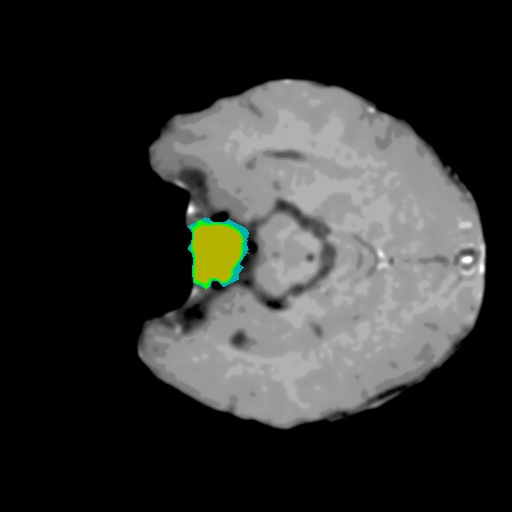

Extensive experiments have been performed in the current setup, and experimental outcomes are reported with the demonstration of numerical and statistical analyses using the proposed QFS-Net, QIS-Net [39], convolutional U-Net [18] and Residual U-Net (URes-Net) architectures [20]. The human expert segmented skull-tripped contrast enhanced DSC brain MR input image slices of size and ROIs are provided in Figure 5 as samples. The demonstration of QFS-Net segmented images followed by the essential post-processed outcome on the slice no. for class level with four distinct activation schemes () are shown in Figure 6. It is evident from the experimental data provided in Table LABEL:tab1 that the proposed QFS-Net performs optimally for the -connected quantum fuzzy pixel information heterogeneity assisted activation () with and gray scale set in comparison with other thresholding schemes and gray scale sets under the four evaluation parameters () [44]. The segmented tumors obtained using the proposed self-supervised procedure under class transition levels with four different thresholding schemes , , and are demonstrated in Figures 7- 8 for the class boundary sets and [39], respectively. The segmented images using the remaining two class boundary sets ( and ) [39] are provided in the supplementary materials section. The segmented ROIs describing the whole tumor region after the masking procedure using QIS-Net, U-Net and URes-Net are also reported in Figure 9.